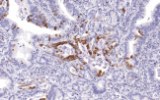

Primary antibodies for immunohistochemistry (IHC) with CE/IVD marking are essential reagents in diagnostic and research pathology, enabling the specific detection of target antigens in formalin-fixed paraffin-embedded (FFPE) tissue sections.

- In gastrointestinal stromal tumors (GISTs), KIT (CD117) expression is reliably detected by IHC, while PDGFRA mutations are evaluated through molecular testing, aiding in targeted therapy decisions.

Beyond diagnostic classification, IHC contributes to prognostic assessment and guides personalized therapeutic strategies in GI oncology.